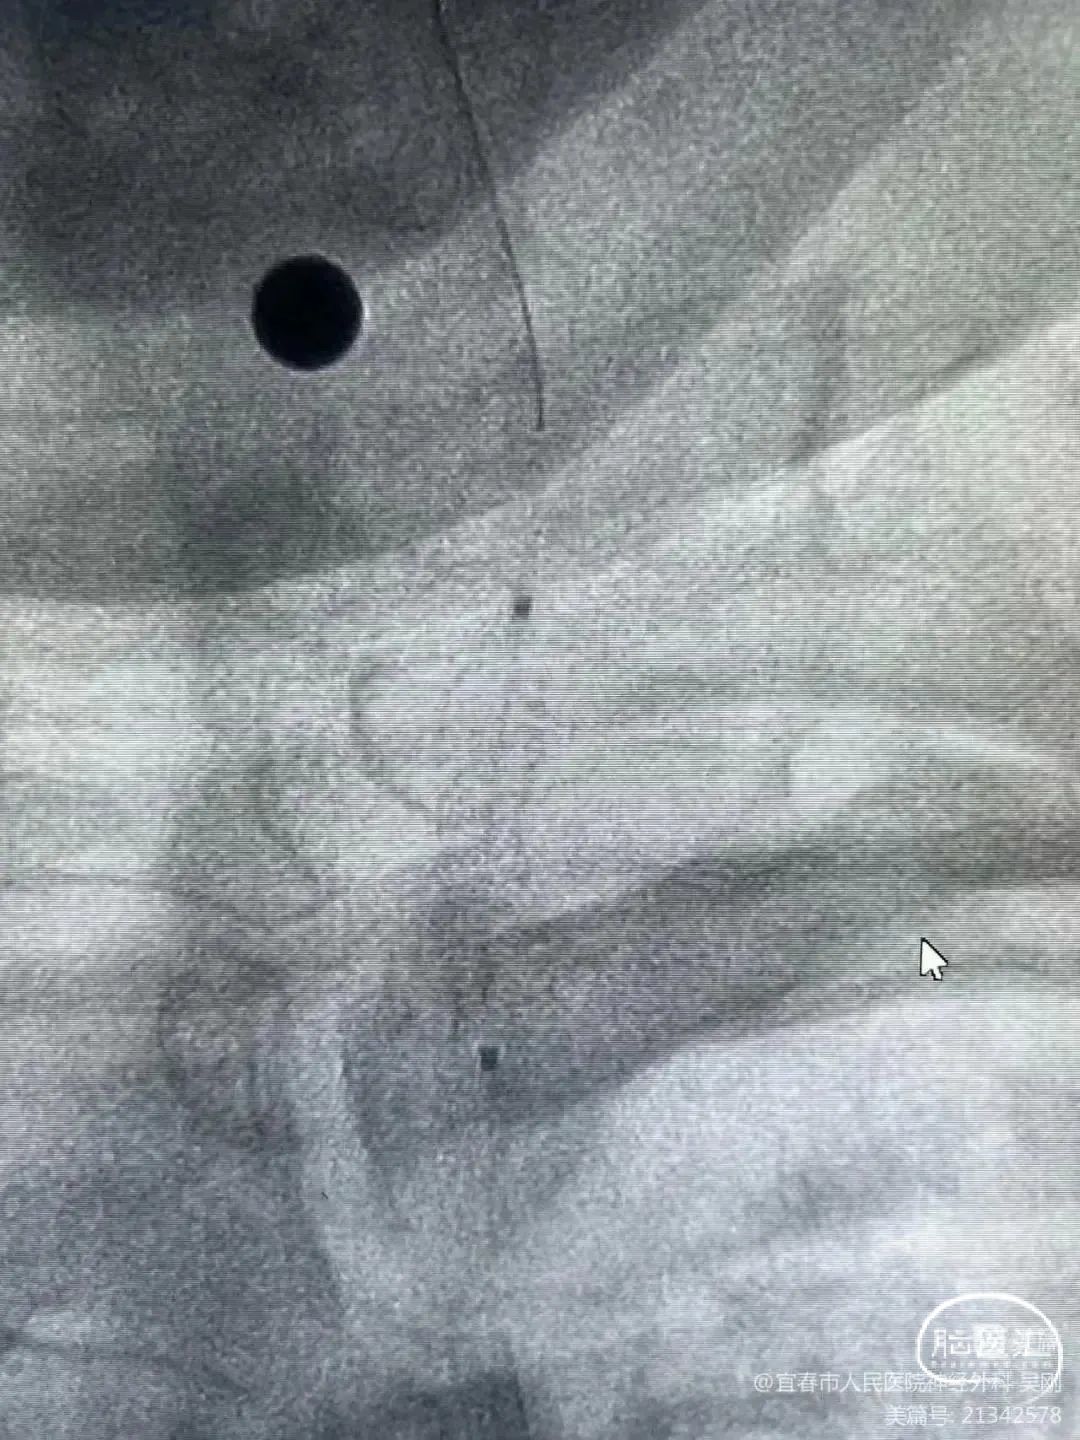

术前DSA影像

右侧颈内动脉起始部中度狭窄,未见血流向后循环代偿。

左侧颈内动脉造影提示后交通开放,代偿供应后循环。

左侧椎动脉开口重度狭窄,前向血流缓慢,V4闭塞。